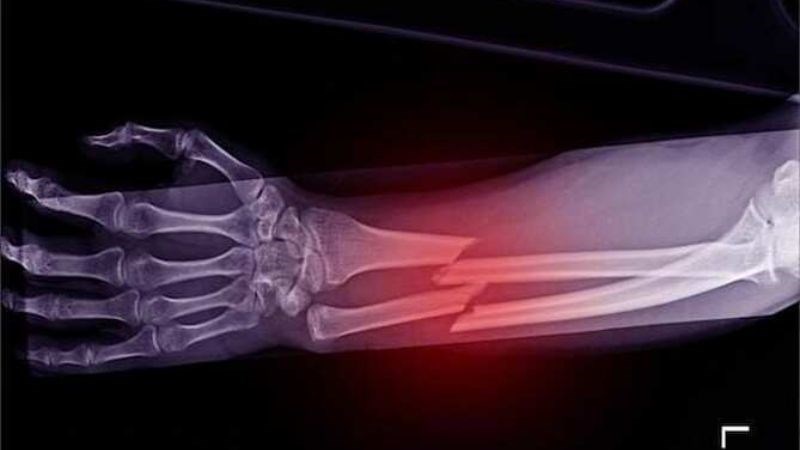

- X - quang: Thông qua hình ảnh trên phim X - quang, xác định vị trí xương bị biến dạng hoặc tổn thương.

Phẫu thuật thường được chỉ định khi gãy xương nặng hoặc biến dạng nghiêm trọng